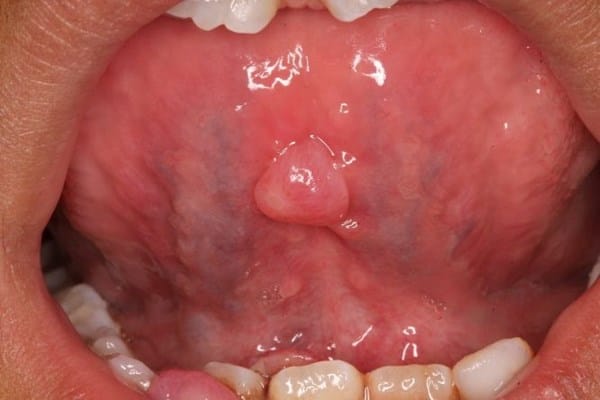

Bulto en la zona sublingual de la lengua

I. Hola Compañer@, por mi parte sólo soy lector, pero en base a asemeja a un cuadro de Mucocele (inflamaciones pequeñas de glándulas salivares) o un quiste diapneusico, que és básicamente un cuadro hermano, pero sin verlo pienso es difícil de precisar, ¿podría decirnos si es blando al tacto o presenta resistencia/dureza?. Para facilitar la respuesta de un experto o profesional, por favor suba una captura de la zona si le fuese posible, podría hacer utilizando esta página, https://postimages.org/

Quisiera trasladarle un poco de información sobre mucocele/quiste diapneusico

He leido que una alergia a determinados alimentos o bebidas tambien es posible, en este caso, los bultitos suelen tener un color rojizo o amarillento y suelen doler. Se recomienda, en general, tomar helados y comidas frías para paliarlo, aunque deberá responderle un profesional.